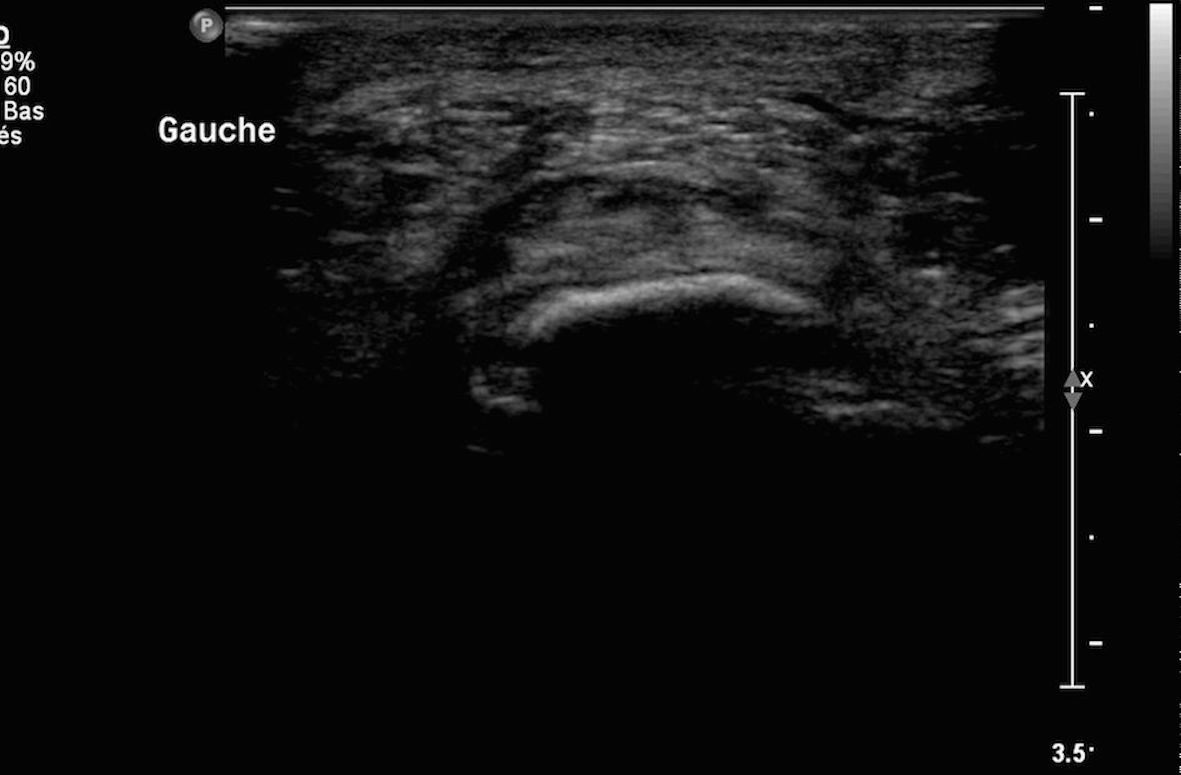

Infiltration d'une bursite calcanéenne sous contrôle échographique image 1

Images 2, 3 et 4 aiguille en place dans la zone hypodense (burste) sous deux incidences orthogonales